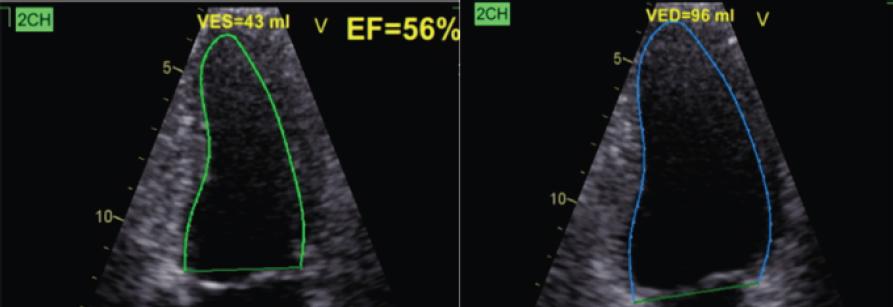

Figure 1